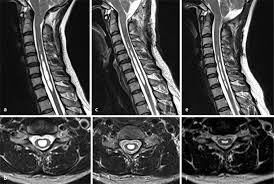

Es kann vorkommen dass nach einer Wirbelsäulen OP Narbengewebe die Nerven bedrängt und das zu erneuten Schmerzen führt. Diese treten typischerweise einige Zeit nach der Operation auf Narben brauchen Zeit sich zu bilden.

Mrt Diagnostik Von Degenerativen Veranderungen Der Wirbelsaule Springerlink

Postoperative Befunde An Der Wirbelsaule Springerlink